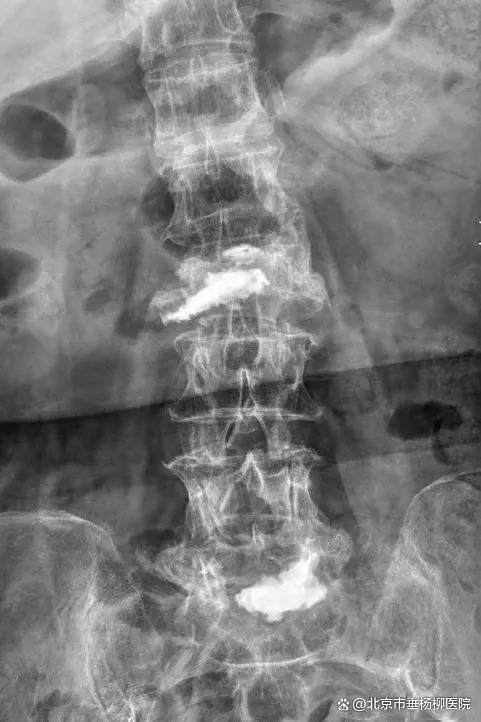

经过3个小时的手术,患者手术顺利,椎体内骨水泥弥散良好,椎管内神经减压彻底。术后患者恢复良好,当天即感觉疼痛缓解。经过2天的术后治疗,患者已经可以正常行走。术后3天,患者平安出院,后续接受康复治疗。

▲术后X线,椎体内骨水泥弥散良好